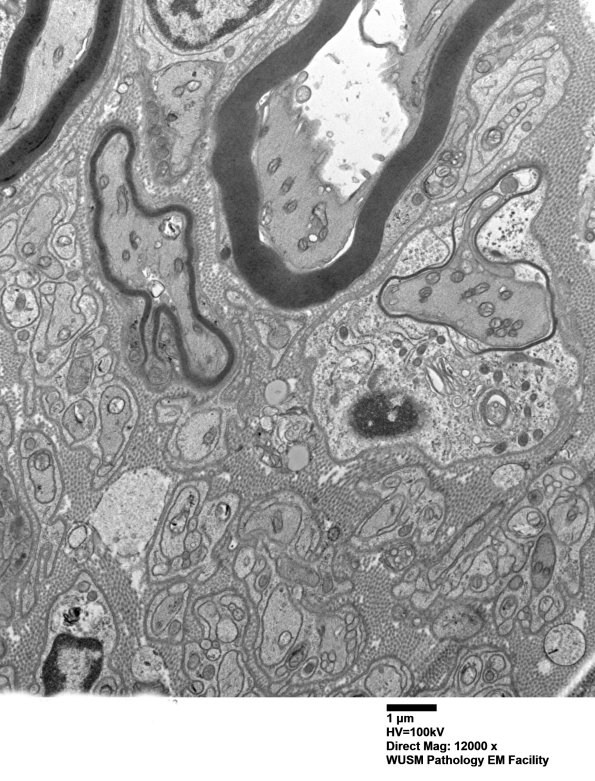

Washington University Experience | PERIPHERAL NEUROPATHY | 1 NORMAL NERVE ANATOMY | 6 Infant Peripheral Nerve | 2B9 W20-132 A (Case 2) tibial_013 - Copy

2B9,10 Additional thinly myelinated developing axons are identified. (electron micrograph)